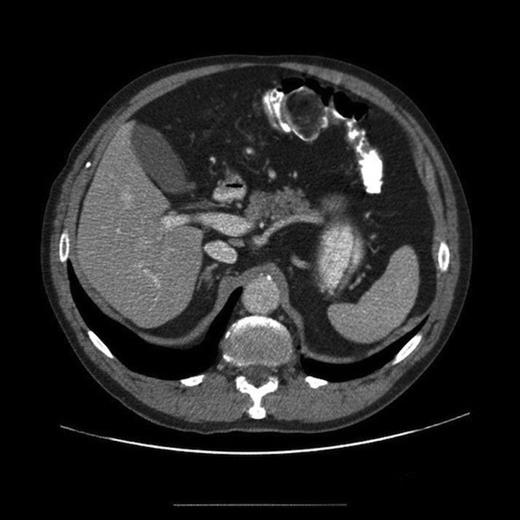

Histology from biopsies taken showed no evidence of neoplasia or dysplasia but was felt to most likely be unrepresentative of the endoscopic lesion. A staging CT scan of chest, abdomen and pelvis was arranged as part of pre-operative staging protocol and this demonstrated a large 3.3 x 4.3 x 3.4cm heterogeneous enhancing colonic polyp, which predominately enhanced with fatty attenuation (Figure 2). Proximal to the lesion was circumferential colonic wall thickening and surrounding fat stranding suspicious of colonic malignancy. A small node was seen in the vascular pedicle. No distant metastases were identified. There was concern about colonic malignancy and following discussion at a MDT meeting he was offered a surgical resection.